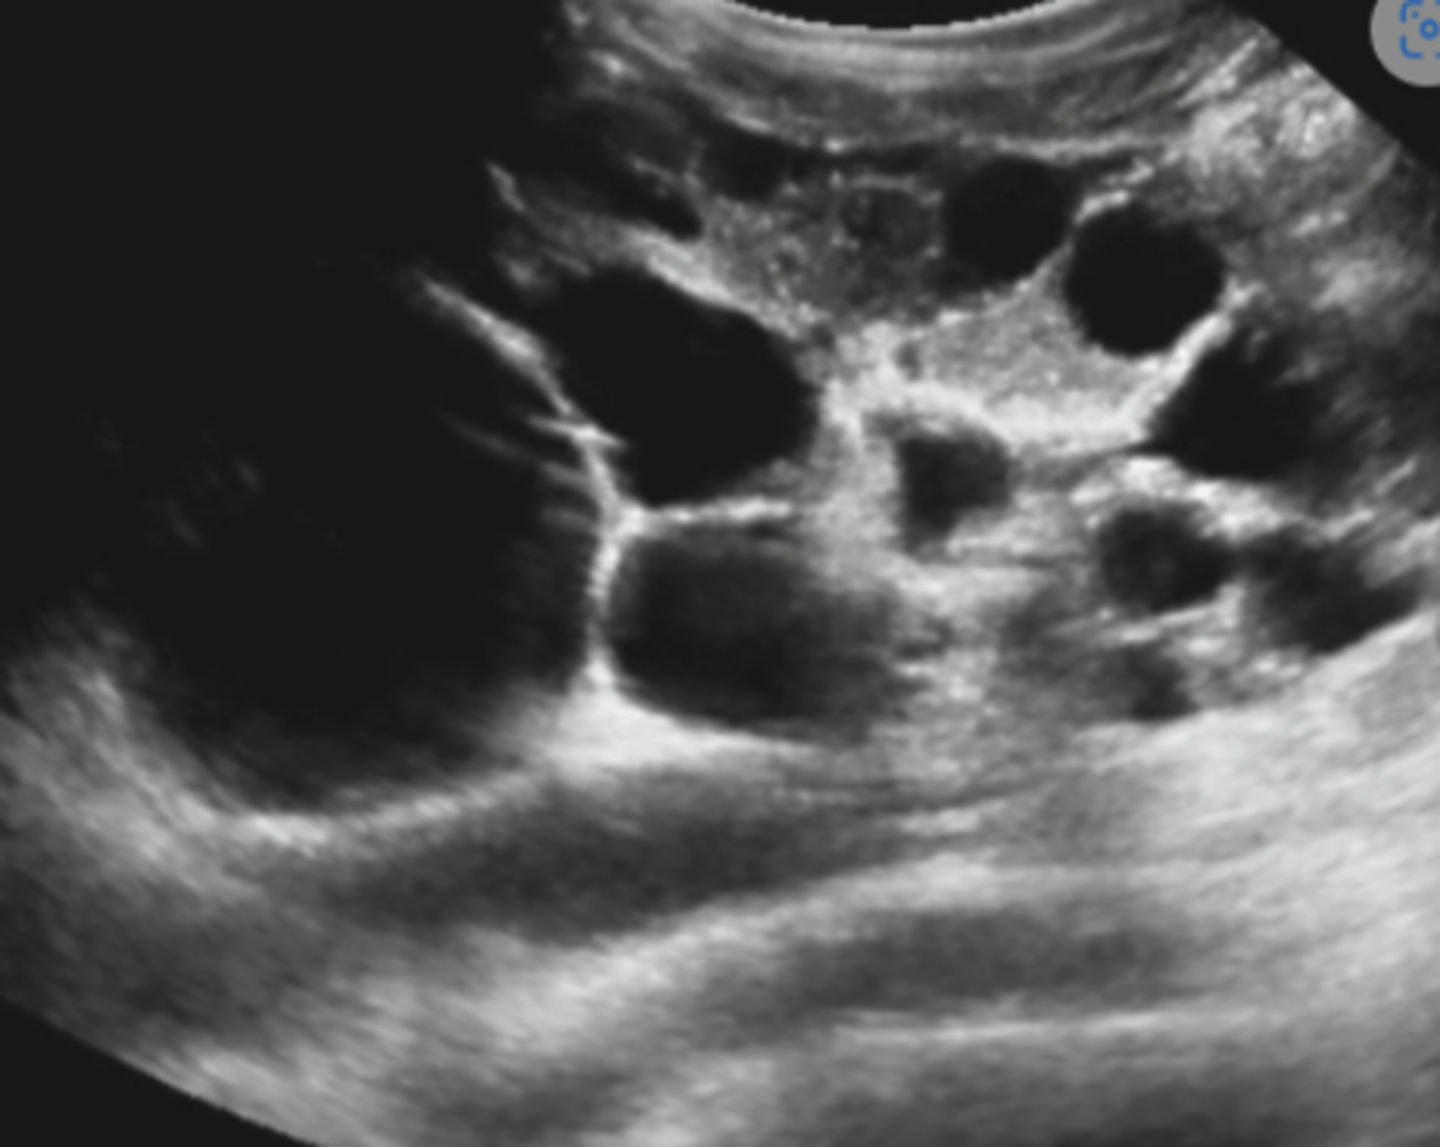

If a patient has autosomal dominant polycystic kidney disease, what will that look like?

Kidneys become enlarged and are slowly replaced by large cysts

Autosomal dominant polycystic kidney disease

When is autosomal dominant polycystic kidney disease usually diagnosed?

30s-40s

What are onset symptoms of autosomal dominant polycystic kidney disease?

Hypertension and renal failure

___% of patients with autosomal dominant polycystic kidney disease will also have ___ ___

50, liver cysts